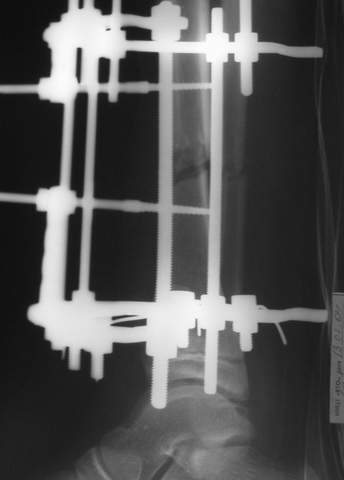

Под рукой прилагаемый пример. Как видите, "стриптиз-аппарат" (шутка проф. З.К.Башурова): 3 кольца-2 кольца-2 полукольца. В случае, который представил Евгений, характер повреждения позволил бы сразу использовать аппарат на основе 2 колец; в крайнем случае прокс. опора м.б. демонтирована сразу после репозиции.

LNS> Под рукой прилагаемый пример. Как видите,

Исходя из него главное преимущество "двух полуколец" - это полный объем сгибания в

коленном суставе, но...

незначительно он отличается от варианта "два кольца"...